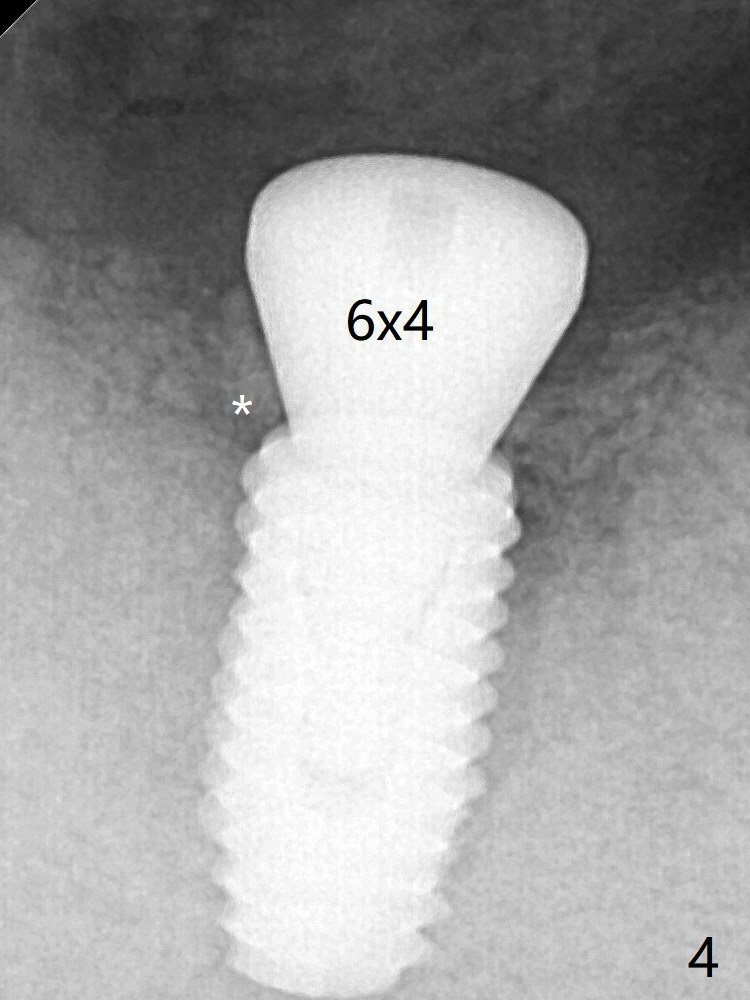

Guided surgery resumes as planned to remove the lingual and apical bone. The buccal bone looks porous from the osteotomy opening. Mixture of autogenous and allograft is packed against the bone plate from the osteotomy before implant placement, but the 5x10 mm implant is unable to be seated completely. After removal of the bone graft from the osteotomy site and use of 4x11.5 mm drill for ~ 1 mm, the implant is seated with ~ 60 Ncm (Fig.3). With buccal incision, bone graft is placed over the distobuccal exposed implant thread (Fig.4 *) following placement of a 6x4 mm healing abutment. The longer healing abutment remains seated (Fig.7 <) without interference from the crest (*) 4.5 months postop. Post-Implant Bone Graft Last Next Xin Wei, DDS, PhD, MS 1st edition 12/23/2019, last revision 01/08/2020